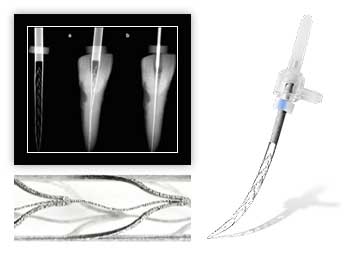

Исправление прикуса у детей

- Пластинка для зубов

- Установка брекетов подросткам

- Индивидуальные капы (спортивные) для защиты от травм зубов

Исправление прикуса детям и подросткам

Изготовление пластинок для исправления прикуса

Коррекция прикуса с использованием съемных и несъемных конструкций, окклюзионная каппа для лечения дисфункции ВНЧС (СПЛИНТ)

фиксация вестибулярных брекетов в полости рта (за 1 челюсть)